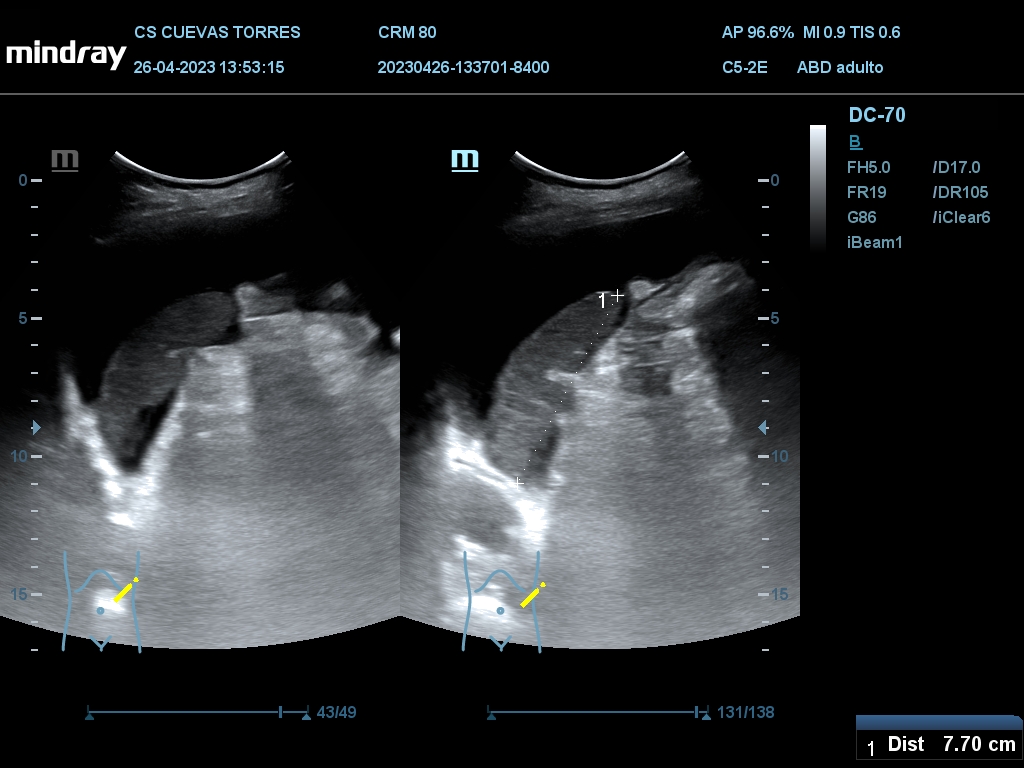

En la ecografía clínica observamos claramente la presencia de líquido libre desde el comienzo de la exploración. Continuando con el estudio Visualizamos circulación portal turbulenta y en el rastreo hepático una lesión ocupante de espacio (LOE) con captación Doppler de 7,45 cm de diámetro máximo.

LOE hepática a estudio.

La paciente fue finalmente diagnosticada de Cáncer de hígado.